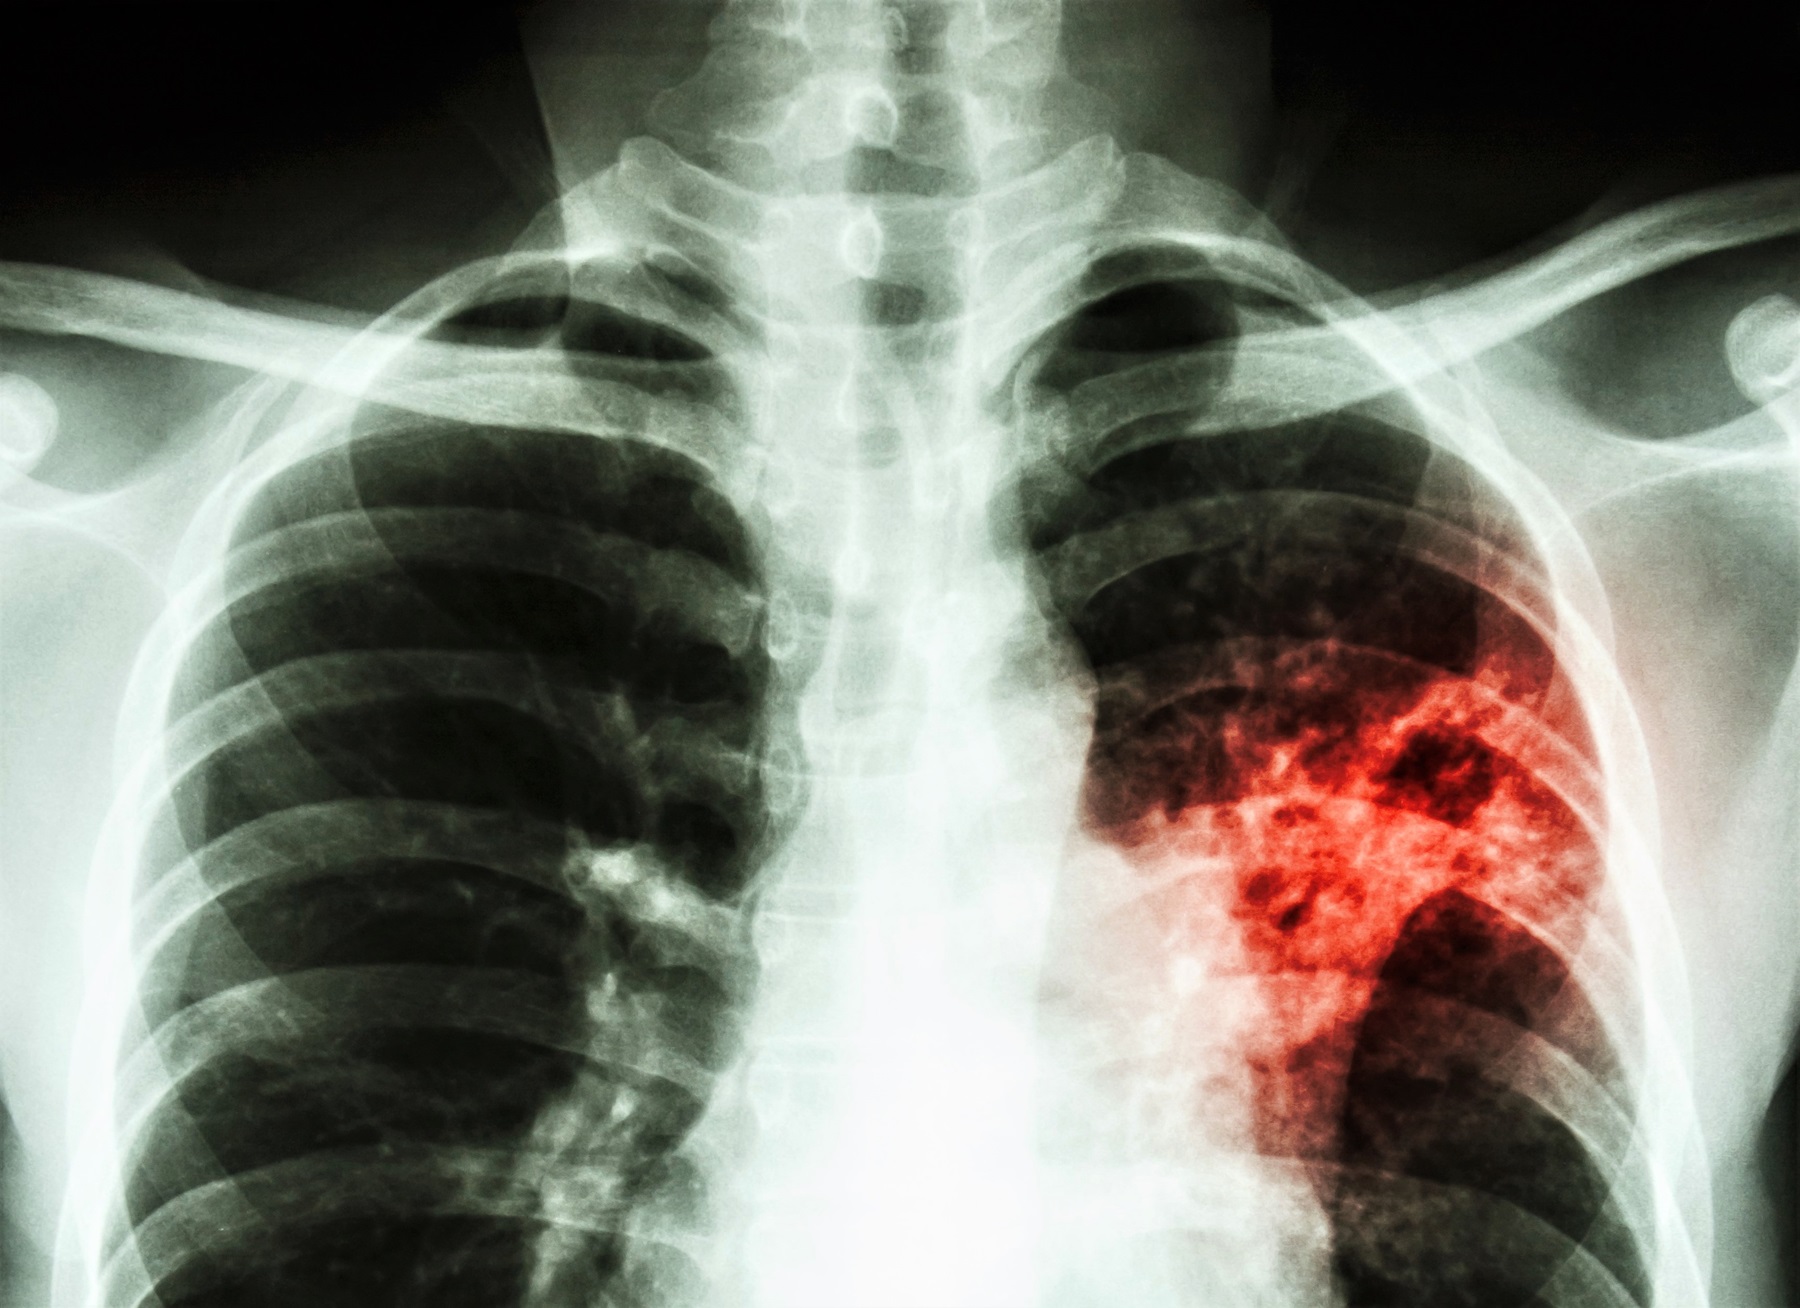

SSI has developed a new test for diagnosing TB (C-Tb). The test can identify the large number of people around the world who are infected with TB and at risk of developing active disease. SSI has now entered into a partnership with Serum Institute of India Pvt. Ltd. (SIIPL) who will be producing and distributing the test. This initiative supports WHO’s goal to reduce the spread of tuberculosis.

There are >1.5 billion people who are estimated to be infected with TB and are at risk of developing active pulmonary TB. In 2016, WHO therefore launched an ambitious strategy focusing on early screening and preventive treatment of infected persons.

Up till now, programmatic implementation to detect and treat latent TB infection has not been possible due to the absence of a cost-effective and reliable test for diagnosis as well as a cost-effective treatment in high volumes. Now, with the availability of the C-Tb and cost-effective drugs it is possible to scale up the detection and treatment of latently infected which will help achieve WHO’s target of eradicating the TB epidemic.